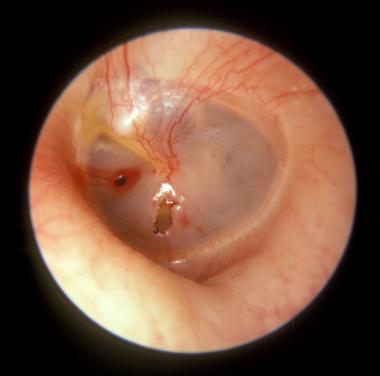

Tear in the thin tissue called the eardrum, which separates the ear canal from the middle ear. It is caused by infection, sudden pressure changes, excessive noise or direct trauma. It is diagnosed by medical examination and confirmed by otoscopy. It usually heals spontaneously, although surgical intervention may sometimes be necessary. For as long as the tear exists, there is a risk of infection and hearing loss.